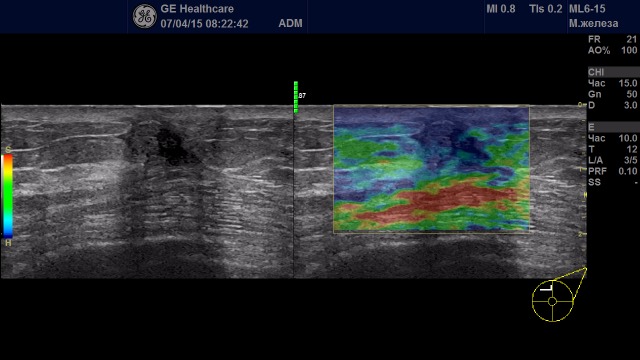

Образования с неудовлетворительной эластичностью (тип IV-V)